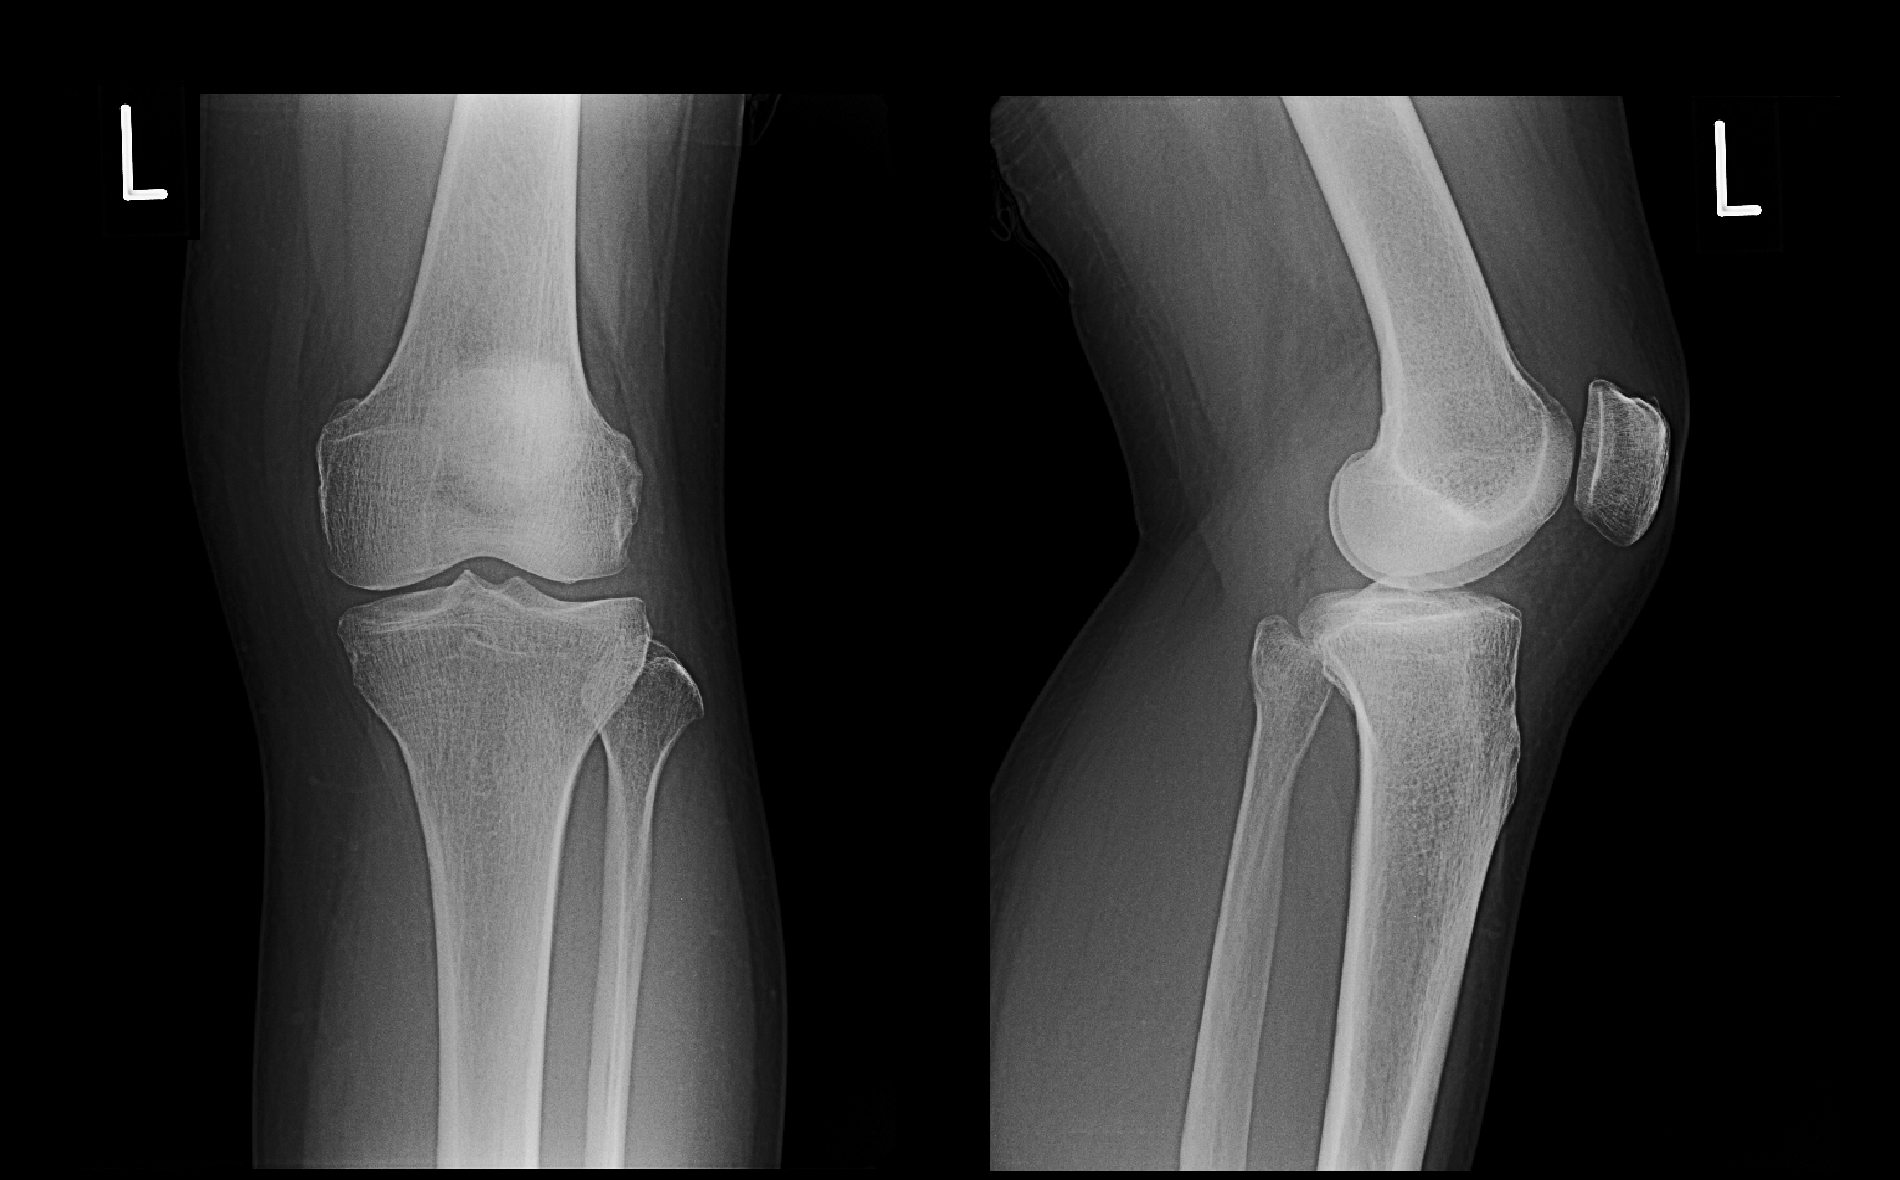

66才の女性で訪問看護師をしていた方です。平成29年ボランティアの会議で6時間座っていて立ち上がりの際に左膝痛が発症し、6月19日に当院を受診されました。左膝は軽度熱を持っており、内側半月板に圧痛を認めました。鎮痛薬と関節の腫脹を軽減するプレドニゾロンという薬を1週分処方して経過をみることにしました。

66才女Xp1.jpg

6月22日車から降りた時に左膝に腫脹感を感じ、その後横断歩道を小走りで渡る時に左膝窩部(膝の背側部です)がギクっとなり、左膝が伸展困難となったそうです。6月23日に当院を受診されました。同日、膝MRI検査を施行しています。